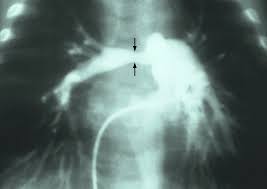

Pulmonary valve stenosis is one of the common issues linked to the syndrome. The condition causes the narrowing of the pulmonary valve. The pulmonary valve is the tissue flap separating the ventricle (lower right chamber of the heart) from the pulmonary artery (the artery supplying blood to the lungs). It occurs alone or along with other heart defects.

The condition can cause narrowing of the artery carrying blood to the lungs for oxygen. The condition is known medically as pulmonary artery stenosis.